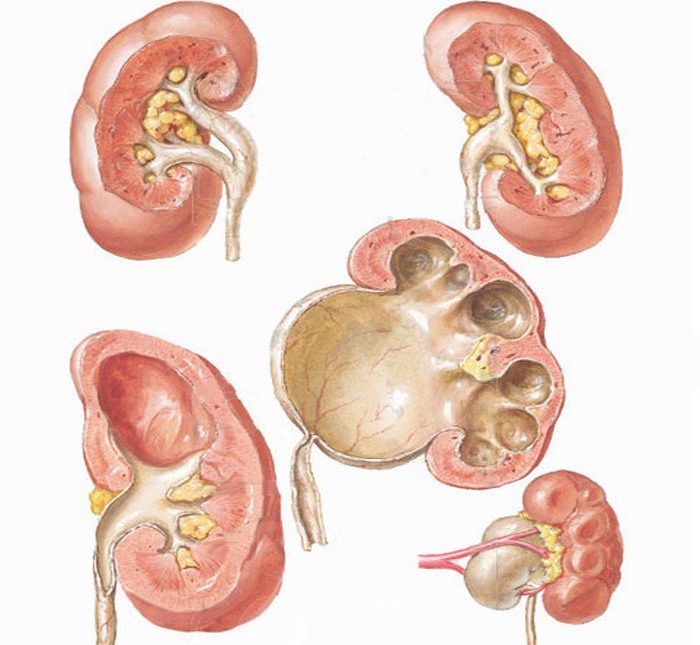

Рефлюксирующий мегауретер: Визуализация и медицинские изображения